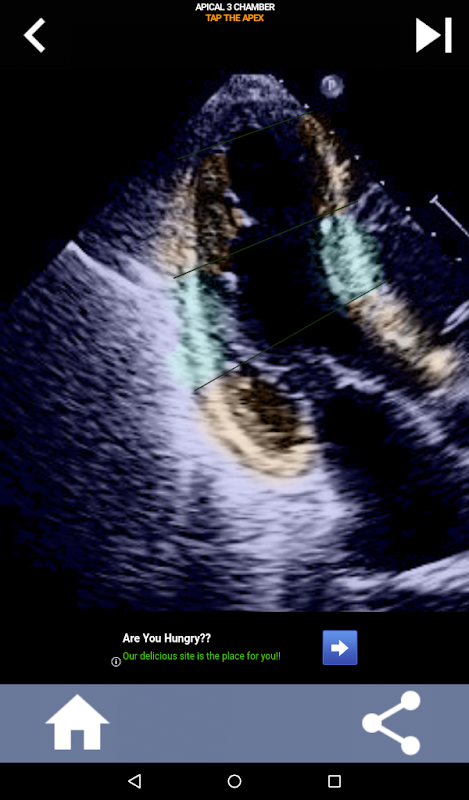

Quiz-gebaseerde visuele benadering voor het leren van de AHA-hartsegmenten: echocardiografie

Het begrijpen van de hartsegmenten van de AHA (American Heart Association) is van het grootste belang voor een cardiale sonograaf om effectief te communiceren met de cardioloog die het rapport schrijft. Door de specifieke anatomische regio's en hun overeenkomstige segmenten te kennen, kan de echoscopist eventuele afwijkingen of bevindingen nauwkeurig beschrijven en communiceren, waardoor een duidelijke en beknopte communicatie tussen beide professionals wordt gegarandeerd.

Dit begrip wordt met name cruciaal wanneer de cardioloog de precieze locatie van een probleem probeert vast te stellen of wanneer de dienstdoende arts een probleem binnen een specifieke regio identificeert, waardoor de echoscopist wordt gevraagd om het overeenkomstige segment nauwkeurig weer te geven, zoals de middelste onderwand. Het hebben van een volledig begrip van de AHA-hartsegmenten is dus een essentiële vaardigheden.

Deze app test je kennis met behulp van echte echobeelden, wat ik vaak de beste lesmethode vind.